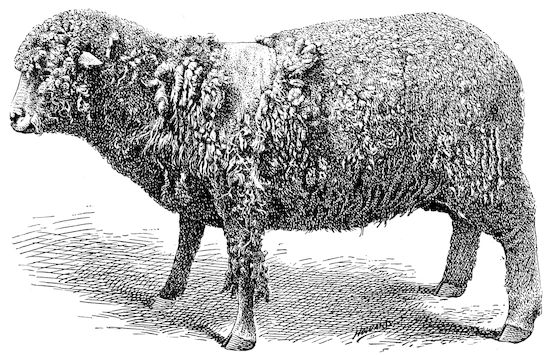

114. The fourth phase, or period of osteomalacia, i.e. softening of the bones, is also the last. It is rarely seen in large animals like horses and oxen, because accidents so often accompany the preceding stages and necessitate slaughter; but it is common in goats and pigs.

In this phase the bones become elastic, soft and depressible, yielding to the pressure of the operator’s fingers.

The flat bones are particularly liable to this change, which is common to domesticated animals. The bones of the head are the first to suffer; later those of the pelvis. The lower jaw becomes swollen, particularly about the centre of the branches which may attain three, four, or five times, their normal thickness.

The depression in the submaxillary space disappears. The upper jaw undergoes similar changes, becoming deformed and thickened until the cavities of the sinuses and the hollow appearance of the palate are lost, while the face is so changed that it cannot be recognised as that of a horse, goat, etc.

The molar teeth are almost buried, their tables alone being visible at the bottom of a depression, the edges of which rise above the neighbouring parts (pig).

Mastication is clearly impossible, the jaws appear paralysed, the muscles powerless, and only swallowing is possible, a fact which explains why life is only prolonged to this stage in animals which can be fed with a spoon or bottle (pigs and goats). The bones of the cranium, although greatly changed in texture, are always less deformed than those of the face.

The changes are such that it is often easy with a mere post-mortem knife to cut the head completely in two. Osseous tissue, properly so-called, has disappeared.

All the constituent tissues, with the exception of the skin and muscles, i.e., the bone, periosteum and aponeuroses, have the appearance and consistence on section of the fibro-lardaceous tissue seen in chronic inflammation.

Osteomalacia, on the other hand, is always well marked.

Regarding the development of the disease in pigs, we may repeat what has just been said respecting the goat. Walking on the knees is often one of the first signs, fractures are somewhat rare, and the period of softening and deformity is always very noticeable.

Fig. 7.—Osseous cachexia: softening of the maxillæ.

18In the final stages, the bones may be cut with a knife, and a time arrives when bony tissue seems completely to have disappeared; thus, as shown in Fig. 8 herewith, it was possible to cut the entire head of a pig into thin slices without the slightest difficulty. All parts of the head had been affected by the softening change.

From the chemical point of view, the diminution in mineral salts and in phosphate of calcium has long been recognised, but the degree of this change varies according to the phase. In human beings the proportions have been estimated as follows: Normal bone, 50 to 80 per cent. of phosphate of calcium; bone in persons suffering from osteomalacia, 5 to 20 per cent. of phosphate of calcium. The changes in the ossein have not been carefully studied. We only know that histologically the ossein becomes fibrillar, and that chemically it no longer retains its normal composition.